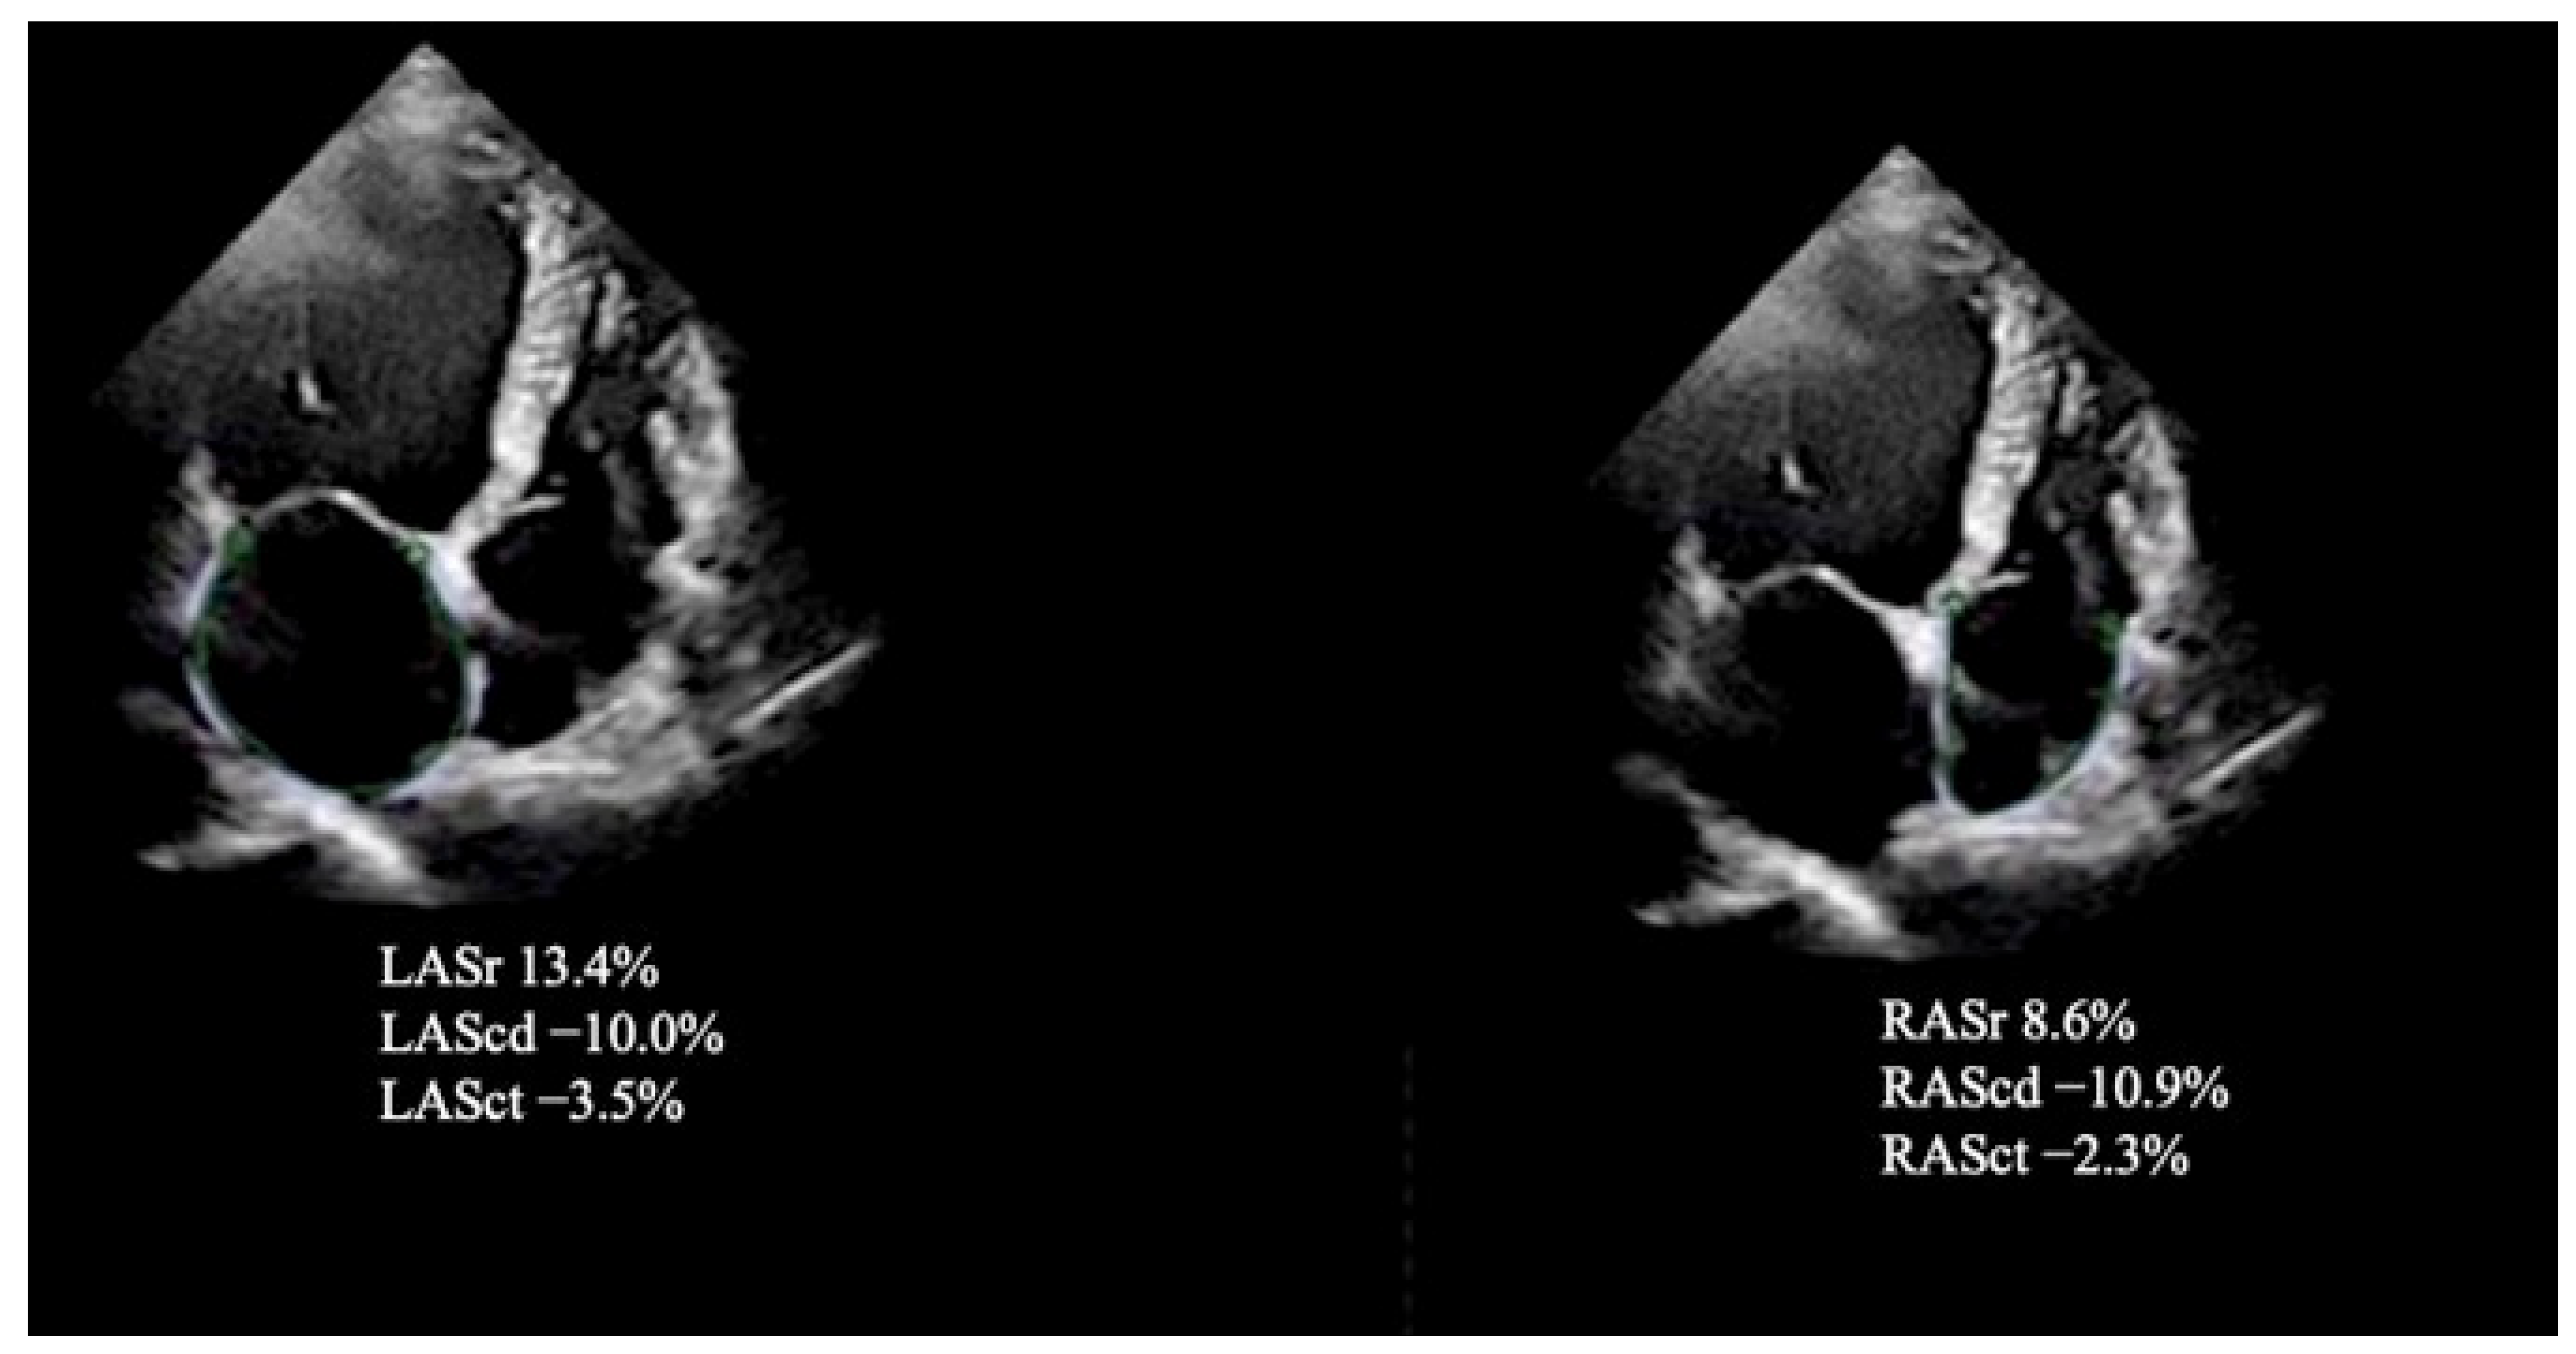

| LAScd, % | −10.7 ± 3.2 | −16.0 ± 4.1 | <0.001 |

| LASr, % | 19.1 ± 6.1 | 27.4 ± 6.0 | <0.001 |

| LASct, % | −8.1 ± 2.6 | −11.6 ± 4.9 | <0.001 |

| RAScd, % | −13.5 ± 5.1 | −18.0 ± 4.8 | <0.001 |

| RASr, % | 26.9 ± 6.4 | 31.6 ± 5.1 | <0.001 |

| RASct, % | −10.4 ± 6.9 | −14.6 ± 3.1 | <0.001 |